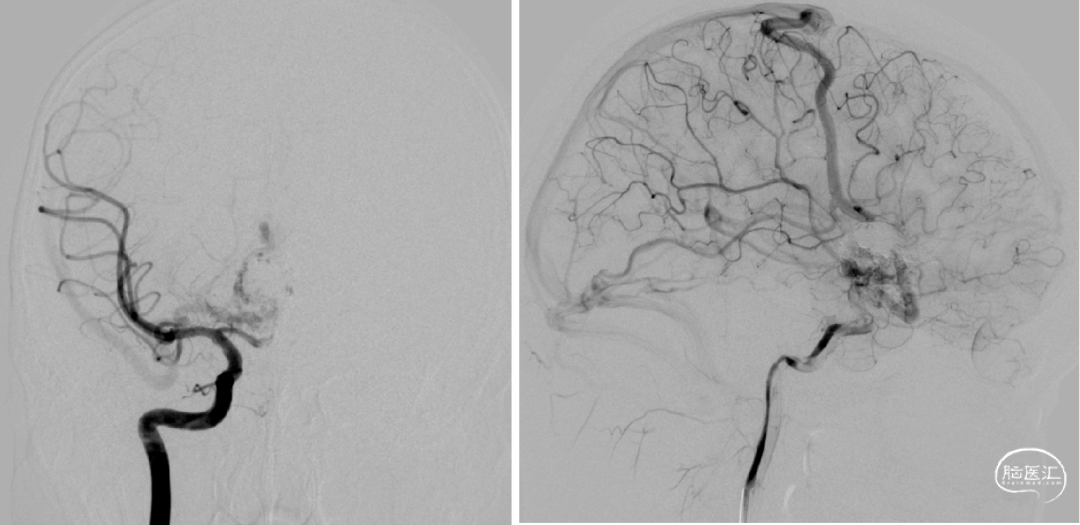

7个月前第一次静脉入路栓塞

术后即刻造影

术前检查